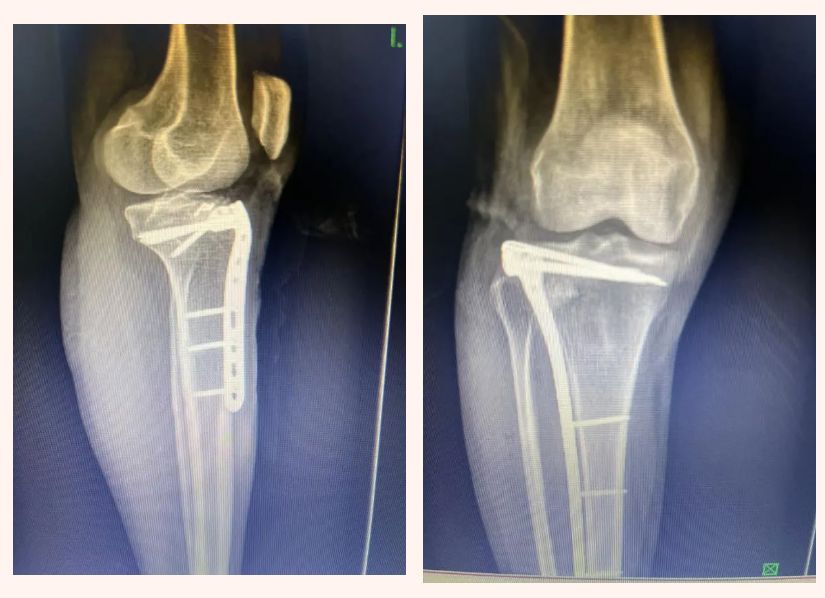

该技术已成功应用于临床,患者欧某因车祸致左胫骨平台骨折(Schatzker分型Ⅴ型),该科医护团队术前制定周密手术方案,采用经关节手术入路的微创方式,既恢复了外侧平台平整度、稳定骨折端,又规避了内外侧双切口带来的巨大损伤与风险。